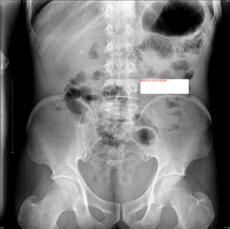

常规腹部摄片并未发现腹腔内有异常密度影,这时我们可不能大意。结石分可透X线的阴性结石和不透X线的阳性结石,不透X线的阳性结石在X线片上呈现较亮的白色影像,很容易被影像医生所发现,而可被X线穿透的阴性结石,则成了漏网之鱼。

吞服钡剂后,钡剂进入胃腔,与周围组织形成密度差,勾勒出胃部形态。钡剂未在胃腔内弥散,未见明确异常征象。

随着体位的改变,钡剂均匀涂抹于胃腔,见胃腔内形成一个类圆形充盈缺损影像,病灶开始露出面目。同时胃腔的充盈缺损影像有多种可能,例如大家最熟悉的肿瘤,那么该如何区分呢?转动体位,有助于鉴别是长在胃壁上固定的肿瘤还是胃腔内可移动的其它东西。

患者做一些翻滚动作后,又加之胃腔内钡剂的排空减少,摄片见刚才的充盈缺损影,变成一枚有薄壳一般类圆形影,如鸡蛋般大小,并随着患者体位的改变而发生位置的变化,这就基本可以肯定它就是真凶:胃结石!